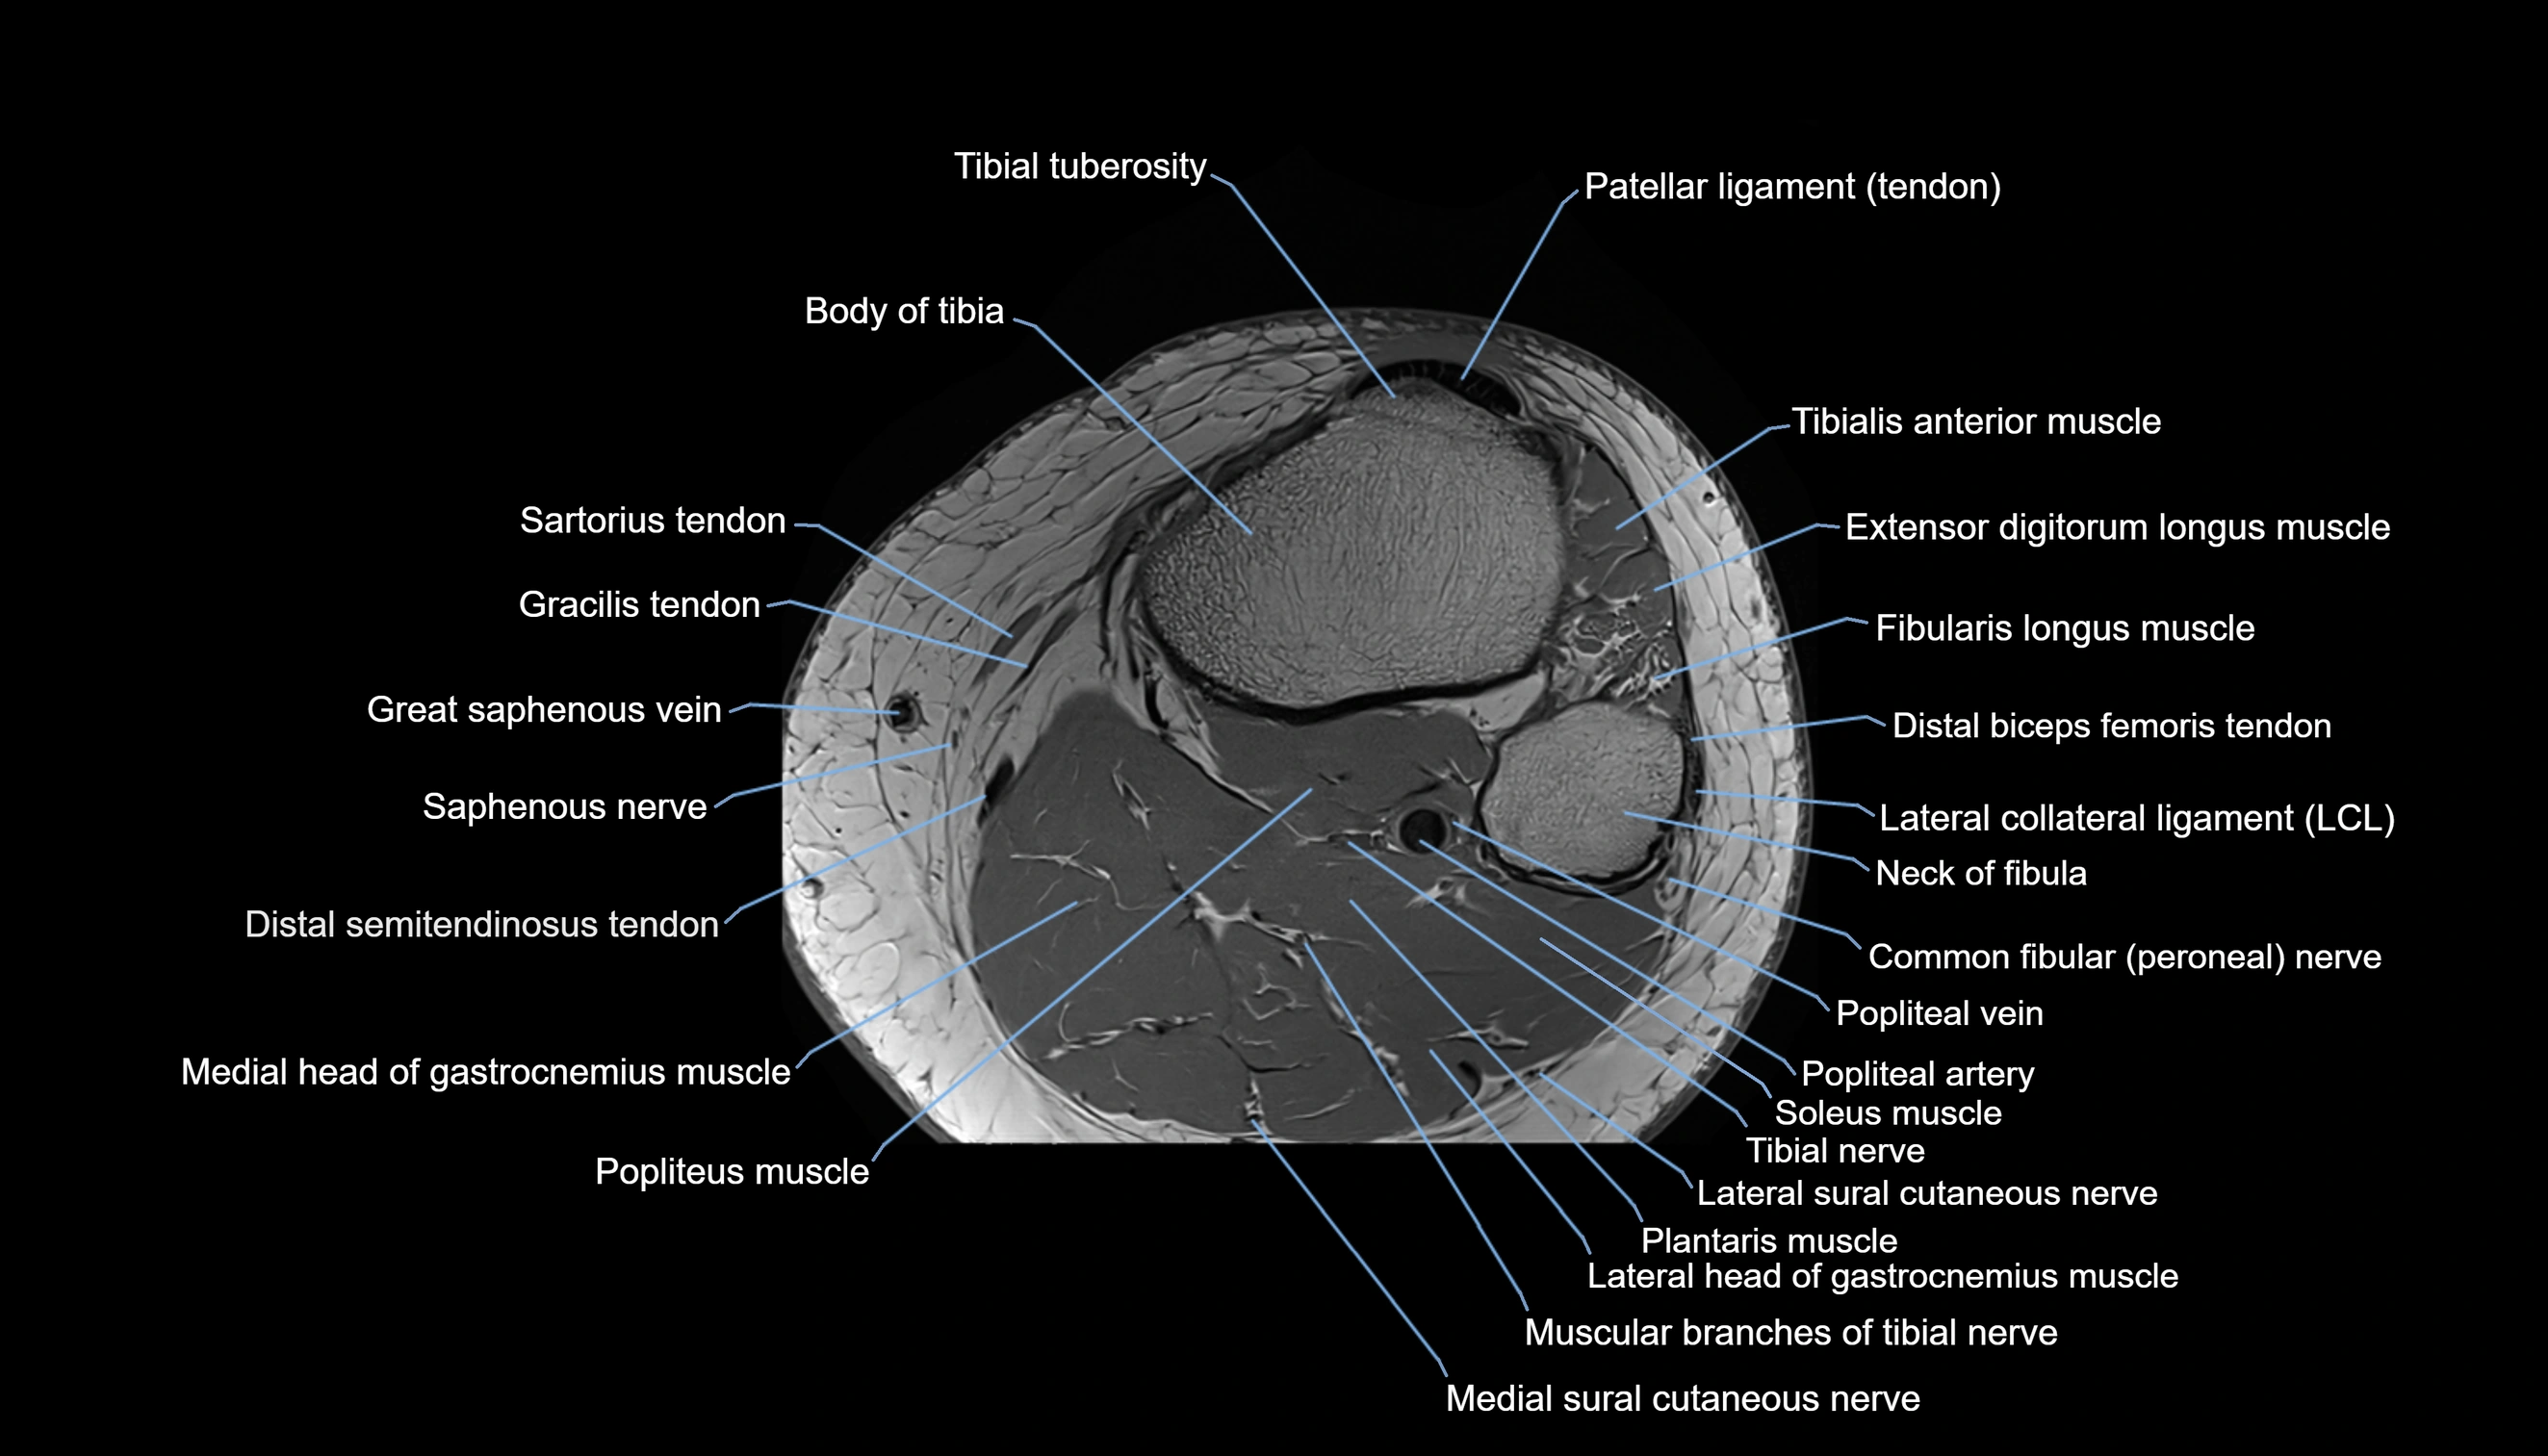

- Body of tibia

- Common fibular nerve

- Distal semitendinosus tendon

- Lateral sural cutaneous nerve

- Medial head of gastrocnemius muscle

- Medial sural cutaneous nerve

- Muscular branches of tibial nerve

- Neck of fibula

- Popliteal artery

- Popliteal vein

- Popliteus muscle

- Saphenous nerve

- Sartorius tendon (Distal)

- Soleus muscle

- Tibial nerve

- Tibial tuberosity

- Tibialis anterior muscle